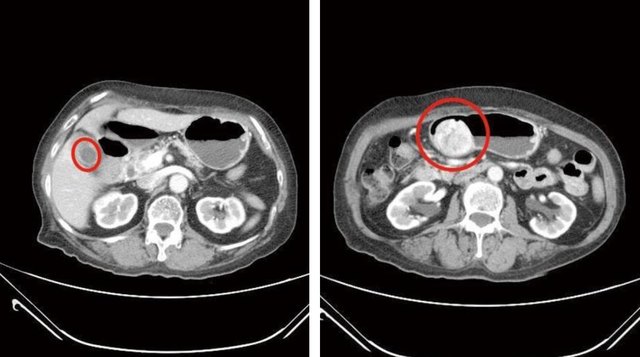

Hình ảnh CT nhân vật bị sỏi và viêm túi mật (trái), đồng thời có khối u mô đệm đường tiêu hóa 6cm trong dạ dày (phải)

Sau khi nội soi tiêu hóa trên và chụp CT, các bác sĩ phát hiện cùng lúc bà gặp phải 2 vấn đề nghiêm trọng trong ổ bụng. Một là sỏi chất đầy trong túi mật và hai là khối u dạ dày loại mô đệm đường tiêu hóa 6cm. Điều đáng nói là khối u này không phải mới xuất hiện mà đã được nghi ngờ từ 3 năm trước nhưng bà Lin không chịu thăm khám chuyên sâu, cũng cho rằng không có triệu chứng khó chịu rõ ràng.